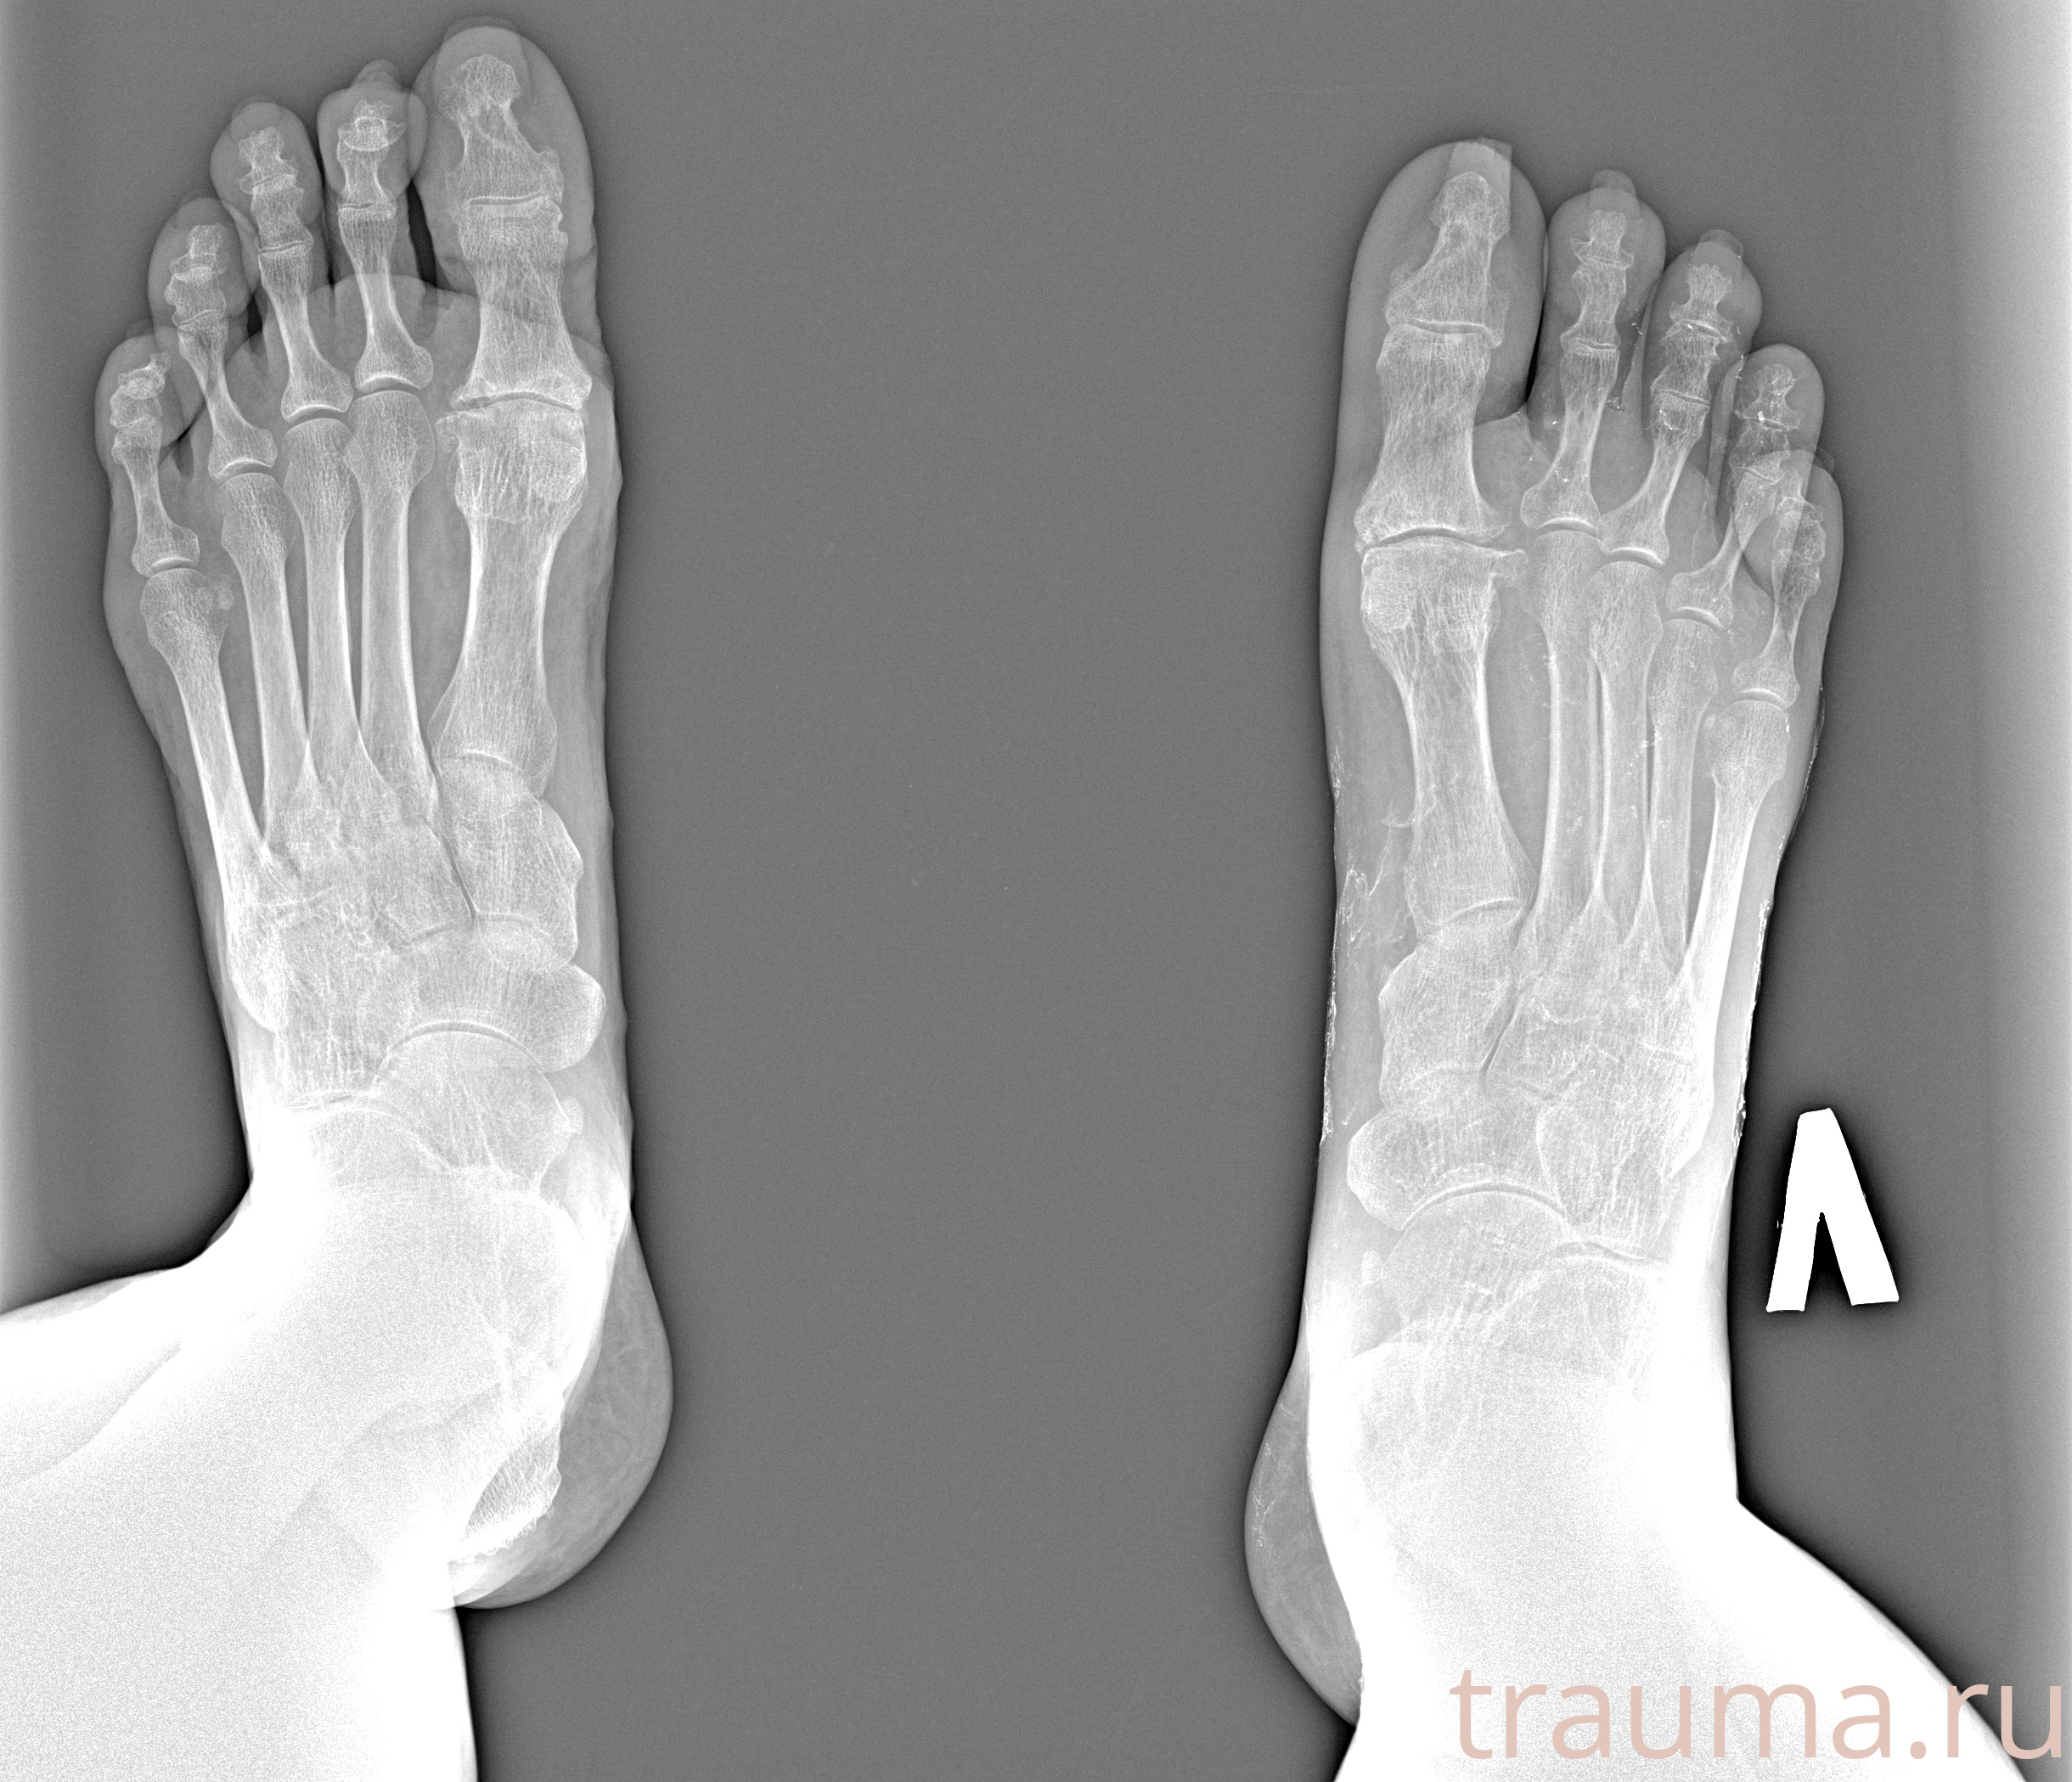

Рентген на дому: по вашему адресу приезжает врач-рентгенолог, травматолог-ортопед с мобильным рентгеновским аппаратом, проводит диагностику травмы или заболевания, делает необходимые рентгенограммы, дает рекомендации по дальнейшему лечению. Получить качественные снимки в домашних условиях возможно благодаря уникальной методике, разработанной МосРентген Центром для института  Склифосовского